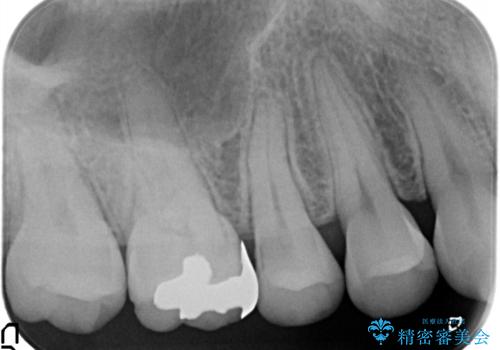

- 虫歯の治療を主訴に来院されました。メタルフリーによる治療を希望されましたので、セラミックインレーにて修復治療を行っております。

- 14万円(セラミックインレー×2)費用は治療当時の料金となります

当院でのセラミックインレーはすべてe-maxと呼ばれる高強度セラミックにて製作されます。

また、製作方法もプレスと呼ばれる方法を用いることで精度を高めています。